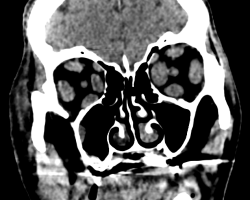

TDM sans injection en coupes axiale et coronale

Présence de gros muscles droits (médial, latéral, supérieur et inférieur) aux deux yeux. Exophtalmie œil droit grade 2, exophtalmie grade 1 pour l’œil gauche (suivant la ligne bicanthale externe). Hypertrophie de l’ensemble des muscles oculomoteurs compatibles avec une maladie de Basedow. Epaississement diffus des muscles oculomoteurs pré dominants sur le droit médial et inférieur